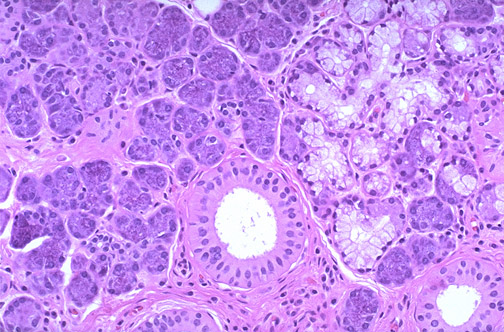

| Normal submandibular salivary gland is shown at medium power, with both serous and mucinous acini. The serous cells contain dark granules from which enzymes such as amylase and maltase are released. The mucinous cells contain pale mucin. The secretions drain into ducts. |